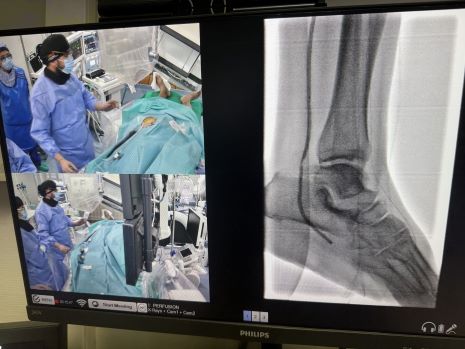

La excelencia del proyecto ha situado al hospital entre los diez centros europeos de aceleración en formación para especialistas en angiología y cirugía vascular y radiología intervencionista. Desde su creación, la Academia organiza de forma periódica cursos y talleres con especialistas de toda Europa, en los que se realizan procedimientos en vivo para mostrar los últimos avances en angioplastias infrapoplíteas, revascularización distal del pie, técnicas de recanalización compleja y punciones retrógradas.

Gallardo destaca además el valor del modelo docente: "En Marbella hemos conseguido crear un espacio de capacitación internacional donde los especialistas pueden implicarse de manera directa en procedimientos complejos. Esa es la clave: no solo enseñar, sino también involucrar en la toma de decisiones durante los casos, porque es la mejor forma de aprender y crecer como profesionales".